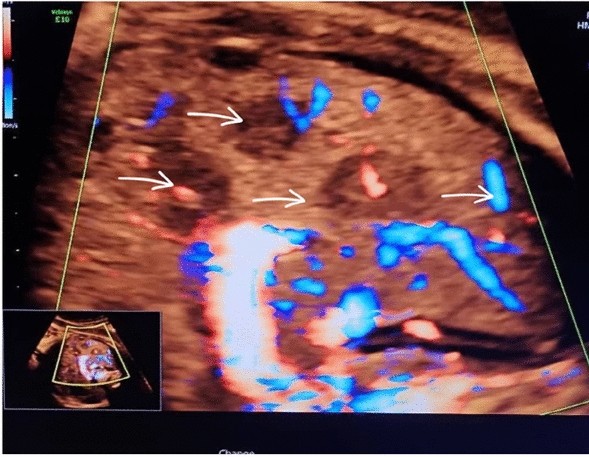

At 37 weeks of gestation, a routine third-trimester ultrasound revealed a hypoechoic lesions in the fetal liver. The lesions were well-circumscribed, measuring approximately 3.5 cm in diameter, and exhibited characteristics suggestive of a vascular tumor. Doppler imaging indicated hypervascularity, raising suspicion for a hemangioendothelioma. Furthermore, the fetal brain appeared normal upon prenatal evaluation. Amniotic fluid levels and fetal growth parameters were within normal limits, and no signs of fetal hydrops were observed. Amniotic fluid levels and fetal growth parameters were within normal limits, and no signs of fetal hydrops were observed. The fetal echocardiogram was normal. Figures 1, 2, and 3

Sagittal view of the fetal abdomen using color Doppler ultrasound, showing vascularity and multiple hypoechoic lesions indicated by arrows